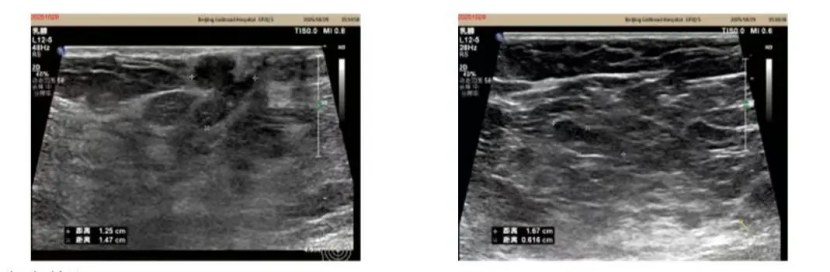

谭水莲到院后迅速投身临床工作,近日成功为一名患者实施超声引导下右侧乳腺占位及腋窝可疑淋巴结穿刺活检术,以实操案例彰显科室超声介入业务的成熟水平。该手术因涉及特殊部位操作与高精度技术要求——右乳乳头旁区域组织敏感、血管密集,腋窝可疑淋巴结位置较深且邻近神经、血管等重要结构,双重考验医生的解剖认知、空间判断与操作精准度。

患者院内检查影像

在谭水莲医生的主导下,团队借助超声实时引导技术,先后完成乳腺占位与腋窝可疑淋巴结的穿刺取样,全程操作流畅高效,无出血等并发症,患者在管床医生李青珊的陪同下安全返回病房,后续将根据活检结果制定个性化诊疗方案。此次高难度手术的高效平稳完成,不仅印证了谭水莲副主任医师扎实的专业功底,更彰显了科室在超声介入领域的精准诊疗能力。